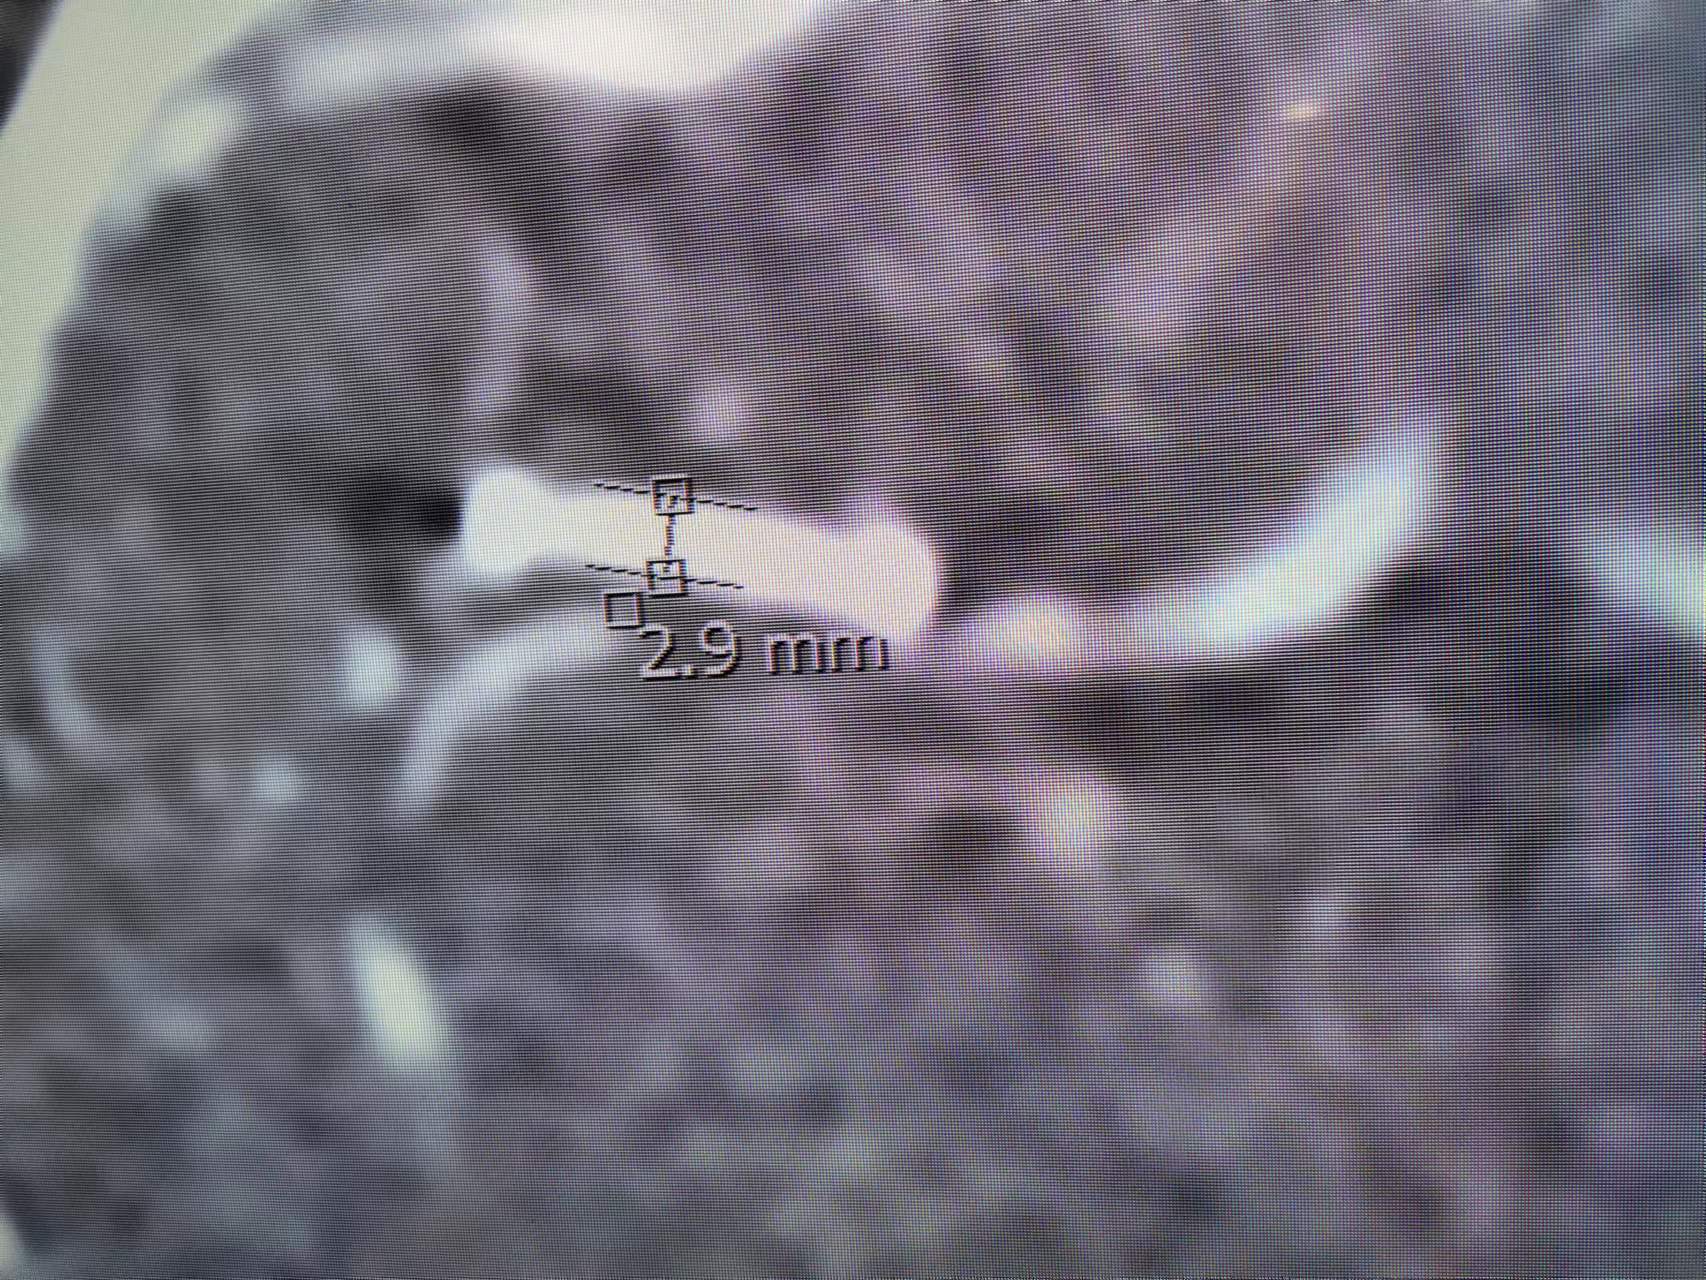

血管直径测量

测量

支架进一步打开,直径改善到2.9mm

进一步打开的支架的形态,打开满意